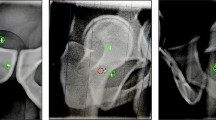

The photon beam was switched off if 5% of the target’s area was located outside of the boundary. The fraction was interrupted by the operator when the target position was outside for too long, thus hindering beam delivery. In these cases, the patient was repositioned and irradiation was resumed. A screenshot of a typical frame from a patient’s cine MRI video is shown in Fig. 1a. In total, 174 cine MRI videos with a cumulative duration of 15.7 h were collected for this study (Table 1).

Extraction of the centroid motion of the target contour in anterior-posterior and superior–inferior directions from the cine MRI data for a typical fraction (patient 1, fraction 3). a Cine MRI frames at the beginning (t = 0 s) and the end (t = T) of the fraction. Target (green) and boundary (red) contours are overlaid on the MR image. The coloured square in the left lower corner shows the beam status (green: beam off, yellow: beam on). b Contour filling and extraction of the centroid position of the target (white cross) and the boundary. c Obtained motion curve of the moving target centroid relative to the static boundary centroid (grey shaded area: beam-on phases). Interruptions in the curves are due to imaging pauses during gantry rotation

The 2D target motion over treatment time t in the AP and SI directions is captured in the (2D + t) cine MRI data. To extract the motion trajectories and the beam status during each fraction, in-house software developed in Python (version 3.8.3) was implemented. With RGB value thresholds, both target and boundary contours were extracted from the video frames. These two contours were then filled homogenously using the watershed algorithm [30]. From these filled contours, the centroid positions of the boundary and the target contours were computed. Finally, the time-resolved relative shifts between the centroid position of the target and the fixed boundary centroid position were calculated. The main steps of the procedure are depicted in Fig. 1. Firstly, the full, non-gated motion was extracted frame-by-frame from the entire cine MRI video for each fraction. Target shifts along AP and SI directions were extracted separately. Secondly, according to the beam status displayed on each frame, the beam-on shifts were selected for further analysis. These corresponded to the residual motion within the gating window, which we labeled gated motion.